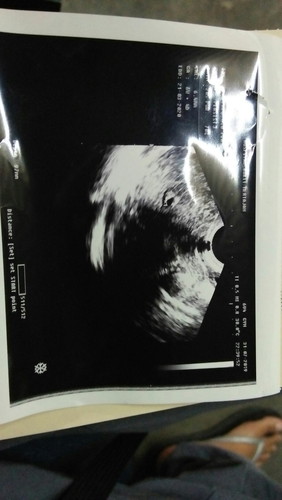

Ada sapa2 kt sni awl khmlan 6@7week bleeding x..smlm doc scan baby ok ada heartbeat dh..doc bg ubat kuat rahim..mmg normal ka??

Normal sis.. jangan risau.. it’s called spotting